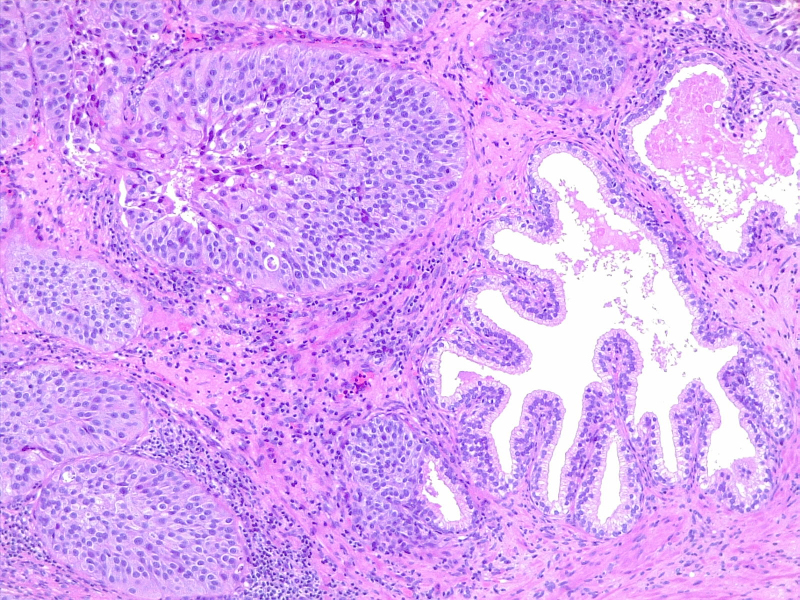

图2:膀胱炎和腺体的原位尿路上皮癌。由维基媒体 CoRus13 提供(公共领域 https://creativecommons.org/publicdomain/zero/1.0/deed.en)